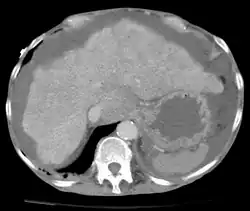

O aumento da quantidade de fluido peritoneal na cavidade peritoneal é conhecido como ascite (do grego askos, "saco"). A origem do líquido acumulado pode variar[1]:

Para confirmação da ascite, realiza-se ultrassonografia como exame de triagem, que revelará o aumento da quantidade de fluido na cavidade peritoneal e permite a escolha adequada do método e local para realização da paracentese. O método é geralmente seguro, mas riscos como desvio da agulha, perfuração de órgãos abdominais e processos hemorrágicos podem eventualmente ocorrer. Não se deve realizar a técnica em pacientes não-colaborativos, com infecções de pele ou gestantes[2].